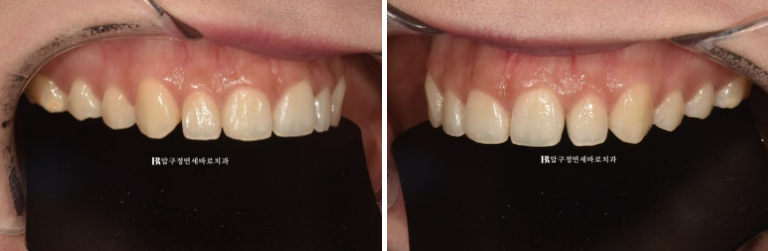

이제 피팅 사진 보겠습니다.

가운데 앞니 두 개가 길어진 것이 눈에 보입니다.

가운데 앞니 두 개는 길게 하고 송곳니로 갈수록 최대한 짧게 하면 스마일라인을 바꿀 수 있습니다.

기존의 편평한 느낌에서 아랫입술과 평행한 예쁜 곡선으로요

스마일라인 하나로 웃을 때 자연스럽고 예뻐집니다.

피팅 하는 날 스마일라인의 디테일한 조절 뿐 아니라 치아 끝단 모양의 동글동글한 정도의 선호도를 반영하여

최종 라미네이트 제작에 들어갔습니다. 환자분은 피팅한 치아모양 보다는 좀 더 동글동글한 느낌을 원하셔서 실제 라미네이트 최종 모양은 다음과 같습니다.